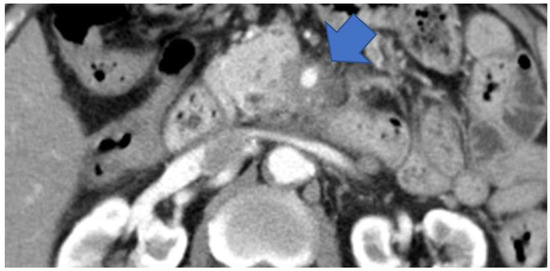

3.3. Imaging Findings